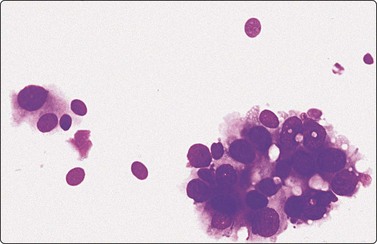

image

Fig. 7.5 Intermediate-grade duct carcinoma

Malignant epithelial cells with intact cytoplasm showing loss of cohesion characteristic of malignancy (Pap, HP).